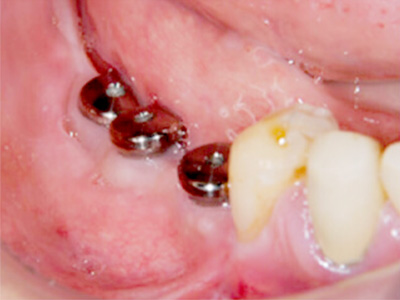

インプラント埋入術後、インプラントが骨に生着したので二次手術を行った後の写真です。

骨吸収の大きかった部位に、きっちり3本のインプラントが植立できました。 -